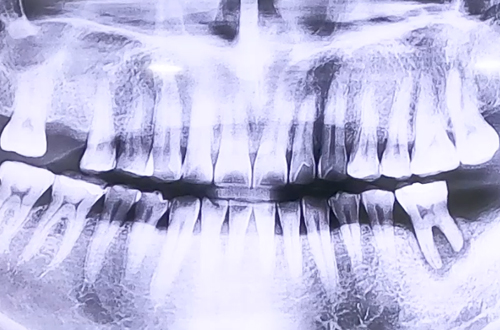

어금니 임플란트 치료 사례

왼쪽 아래 큰 어금니의 통증으로 내원해 주신 환자분이십니다.

진료해 보니 아프신 어금니가 손으로 당겨도 빠질 정도로 심한 흔들림과

많은 염증이 생긴 상태로 확인이 되었습니다.

심한 염증으로 그 부위의 잇몸뼈가 많이 약해져 불안정한 상태였기 때문에

발치 당일 임플란트를 심지 않고 뼈이식까지만 진행을 하기로 하고,

그 뒤쪽 비어 있는 큰 어금니 자리와 발치한지 시간이 오래 지난

오른쪽 위 두번째 어금니 부분에 우선적으로 임플란트를 식립하기로 했는데요.

필요한 임플란트를 심고 발치한 부분의 뼈이식 한 잇몸이 단단히 굳고 염증이 깨끗이 없어지기까지

4개월 정도 기다린 후, 두 번째 임플란트 식립한 뒤 임플란트가 굳기를 기다리는 중이십니다.

음식을 더 편하게 씹으실 수 있도록 오른쪽 위 임플란트를 먼저 보철까지 완성해 드렸으며,

왼쪽 아래 임플란트가 단단히 굳고 보철까지 완성되면 다음 진료일지로 찾아뵙도록 하겠습니다. *^^*